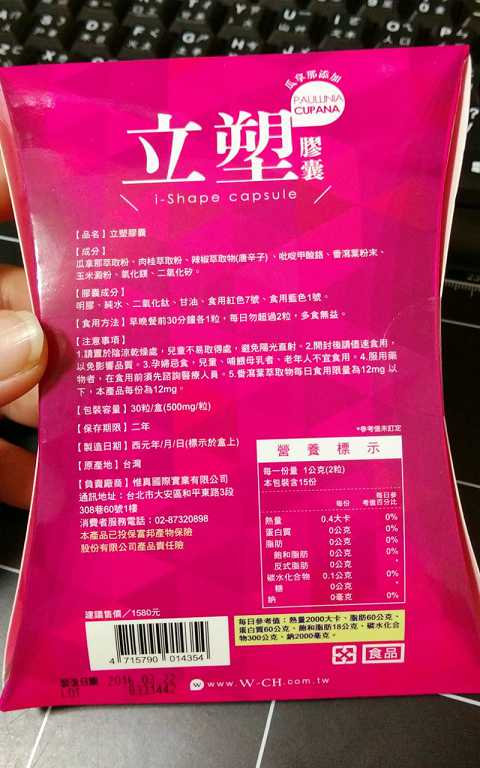

Supercut塑魔纖立塑膠囊的成分有:瓜拿那萃取粉、肉桂萃取粉、辣椒萃取物(唐辛子)、吡啶甲酸鉻、番瀉葉粉末、玉米澱粉、氧化鎂、二氧化矽。

食用方式:早晚餐前30分鐘各1粒,每日不超過2粒。(多食無益)

番瀉葉萃取物每日食用限量為12mg以下,

番瀉葉萃取物每日食用限量為12mg以下,